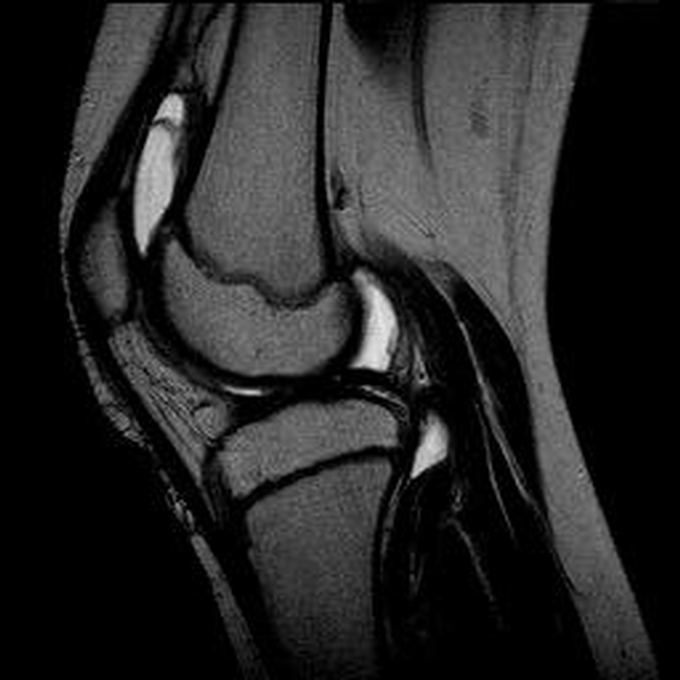

Haemophiliearthropathie bei Haemophilie A.

ARC123 Haemophiliearthropathie bei Haemophilie A.